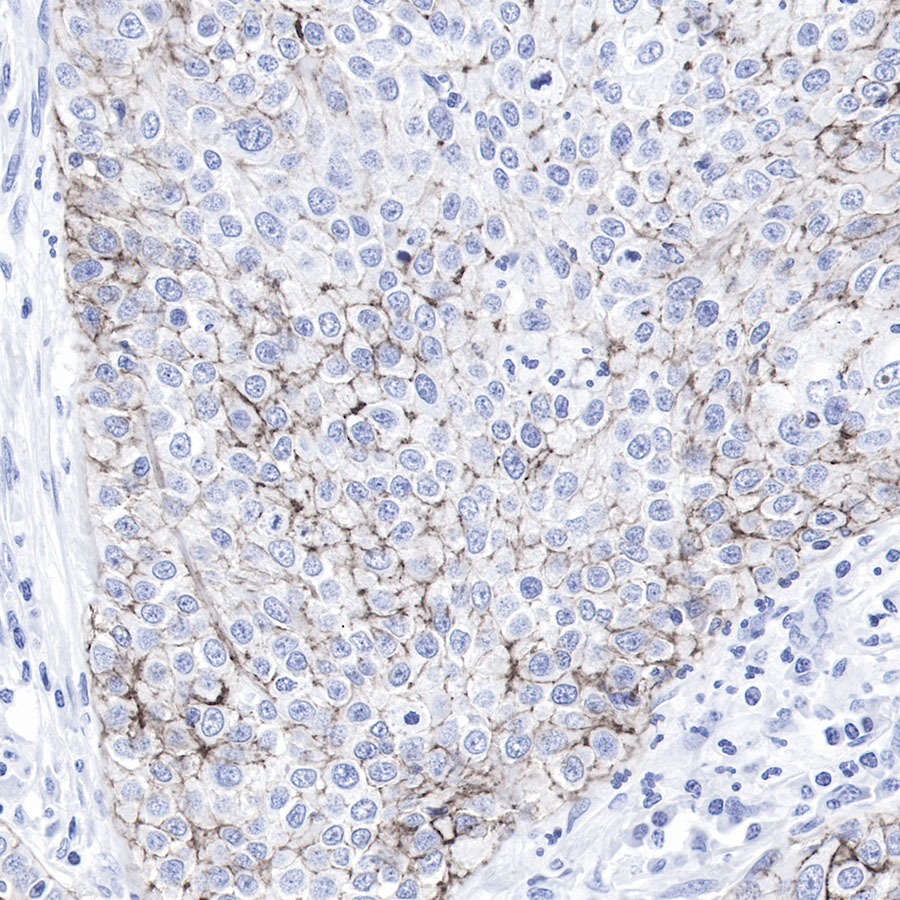

Negative control.IHC shows negative staining in paraffin-embedded human lung adenocarcinoma cancer.

Anti-Claudin-1 antibody was used at 1/500 dilution, followed by a Goat Anti-Rabbit IgG H&L (HRP) ready to use. Counterstained with hematoxylin.

Heat mediated antigen retrieval with Tris/EDTA buffer pH9.0 was performed before commencing with IHC staining protocol.